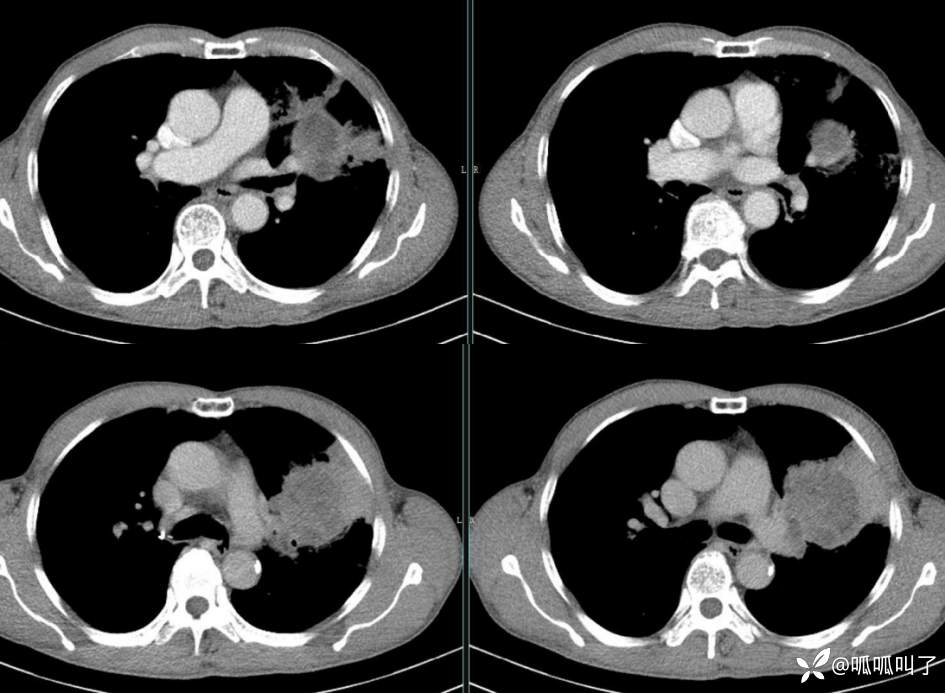

胸部CT平扫和增强: